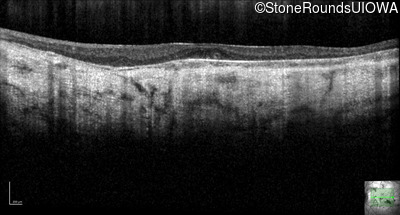

Optical Coherence Tomography - Right - 20/200

Exemplar / OCT Stack

OCT Stack